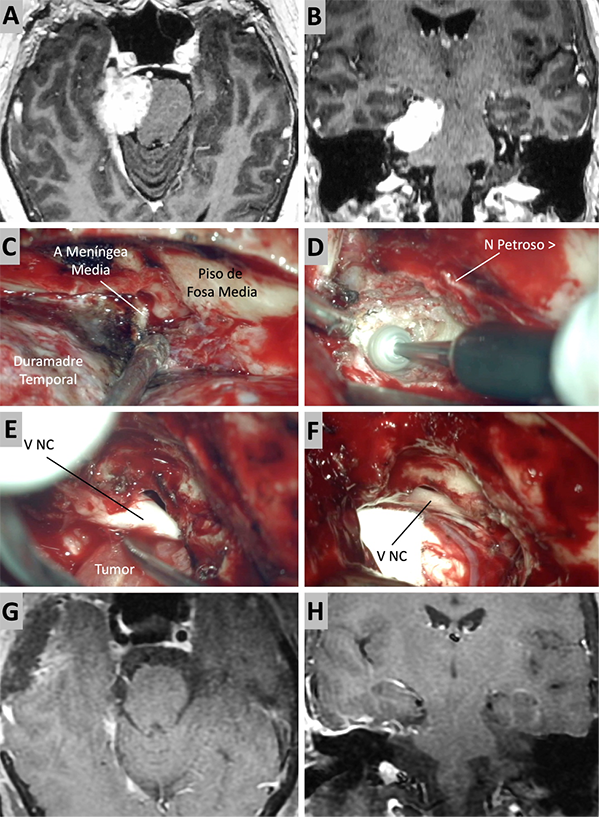

Figura 3. Caso ilustrativo #1. MRPC con implantación petroclival, extensión a la fosa media y compromiso de la incisura tentorial. Paciente con audición conservada. A. Corte axial sobre la región clival media. B. Corte axial sobre la región clival superior. Corte Coronal. D. Corte sagital donde se observa el efecto compresivo sobre el tallo cerebral. E-J. Se realizo un abordaje retrosigmoideo. K-N. Se muestra las imágenes en distintos cortes con el resultado quirúrgico. Residuo tumoral incipiente sobre la incisura tentorial.

Figura 4. Caso ilustrativo #2. MRPC con implantación petroclival, extensión a la fosa media y compromiso de la incisura tentorial. Paciente con audición conservada. A. Corte axial sobre la región clival media. B. Corte axial sobre la región clival superior. Corte Coronal. D. Corte sagital donde se observa el efecto compresivo sobre el tallo cerebral. E-J. Se realizo un abordaje retrosigmoideo. K-N. Se muestra las imágenes en distintos cortes con resección quirúrgica completa.

Figura 5. Caso ilustrativo #3. A-D. Resonancia que muestra MRPC con implantación clival. E-J. Se realiza un abordaje retrosigmoideo, consiguiendo la liberación del complejo VII-VIII del tumor y su resección completa. K-M. Resultado imagenológico postquirúrgico.

Figura 6. Caso ilustrativo #4. Meningioma de la MRPC con implantación petrosa anterior. El paciente presentaba neuralgia del trigémino atípica derecha. A-D. Imágenes por RMN pre operatorias. E-J. Se realiza un abordaje retrosigmoideo consiguiendo la resección total del tumor. K-M. Con ayuda de endoscopio y lente con angulación de 30º se inspecciona el área sin encontrar remanente tumoral. Se observa liberación del nervio trigémino. K-M. RMN postoperatoria que muestra resección total.